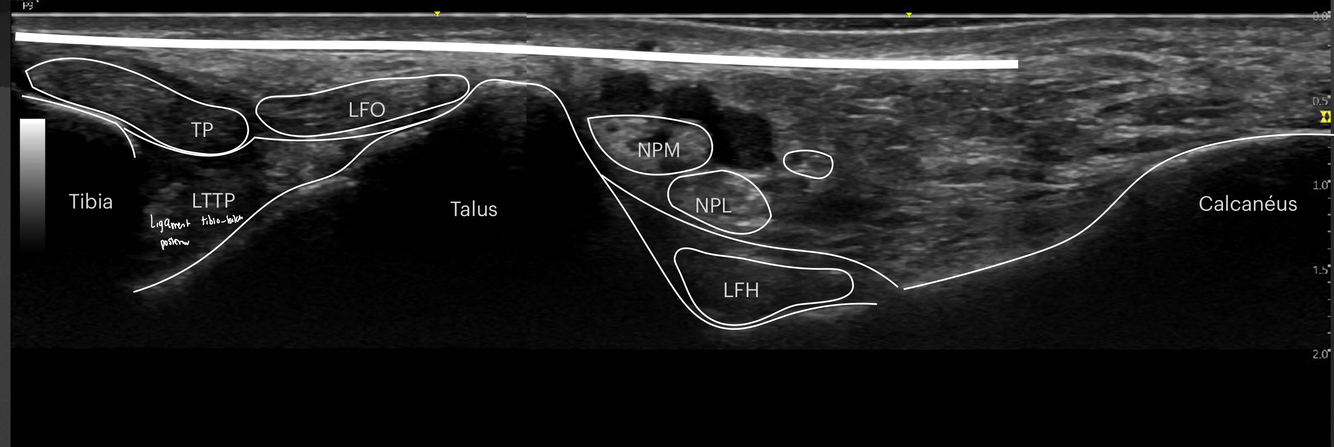

Identifier les structures sur cette image.

Indice: On y voit les os suivants : Tibia, talus et calcanéus

A